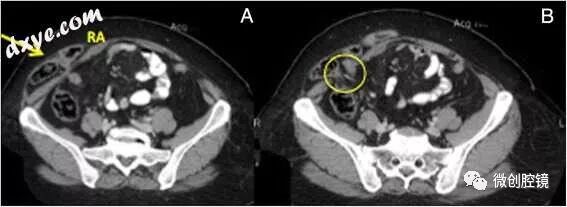

semilunaris)的水平,位于腹直肌的外侧,几乎完全位于脐下,在对应的弓形线水平或以下到后直肌鞘的远端极限。大多数时候疝是顶骨间的,触诊时没有明显的肿块,腹部CT仍然是最好的诊断工具(图12)。虽然非常罕见,但熟悉修复Spigelian疝的不同程序非常有用。腹腔镜IPOM-Plus技术无疑是更容易和更快速的方法,应用与前面讨论的相同的原理。图13提供了修复的良好概述。图12右侧Spigelian疝的CT成像。 a)包含小肠环的疝囊(箭头)(RA:右腹直肌); b)腹壁缺损(O)